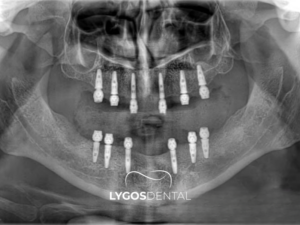

All on Six, tek çeneye altı implant yerleştirilerek sabit protez yapılan tedavi yöntemidir. Bu teknik, tam diş eksikliği yaşayan hastalarda uygulanır. Altı implant çene kemiğine dengeli şekilde yerleştirilir. Daha fazla implant, ekstra dayanıklılık sağlar. All on Six sistemi güçlü çiğneme performansı sunar. Genellikle aynı gün geçici diş takılabilir. İyileşme sürecinde implantlar kemikle kaynaşır. Ardından kalıcı sabit protez uygulanır.

All on Six genellikle şu gruplarda değerlendirilir: Tam dişsiz hastalar, dişleri kurtarılamayacak kadar zayıflamış ve çekim planlanan hastalar, uzun süredir hareketli protez kullanıp tutuculuk sorunu yaşayanlar, alt çenede protezin oynamasından şikâyet edenler, “sabit diş” hissini öncelik yapanlar. Özellikle çiğneme gücü düşmüş, yemek seçmeye başlamış, sosyal hayatta gülerken protez endişesi yaşayan kişiler All on Six’i çok araştırır. Uygunluk değerlendirmesinde hekim birkaç temel soruya cevap arar: Çene kemiği implant için yeterli mi? Diş eti sağlığı stabil mi? Kapanış dengesi nasıl? Hasta ağız hijyenini sürdürebilecek mi? Sigara kullanımı ve sistemik hastalıklar (örneğin diyabet) kontrol altında mı? Bu sorulara net cevap verilmeden “All on Six kesin olur” demek doğru değildir. Çünkü sabit protez, rahatlık kadar sorumluluk da getirir.

Bu iki kavram sık kıyaslanır. Genel mantık olarak All on Four’da bir çeneye 4 implantla sabit bir restorasyon planlanır; All on Six’te implant sayısı artar. İmplant sayısının artması bazı vakalarda yük dağılımını daha dengeli hale getirebilir ve uzun vadede daha “rahat” bir çalışma alanı sunabilir. Özellikle kemik hacmi uygunsa, 6 implantla daha güçlü bir destek elde etmek mümkün olabilir. Yine de şunu açık söylemek gerekir: Daha fazla implant her zaman “daha iyi” demek değildir. Anatomik sınırlar, kemik kalitesi, planlanan sabit dişin tasarımı ve hastanın bakım alışkanlıkları en az implant sayısı kadar önemlidir. Bazı hastalarda 4 implantla mükemmel sonuç alınırken, bazı hastalarda 6 implant daha güvenli bir seçenek olabilir. Kararı belirleyen şey çoğu zaman kemik ve risk profilidir.

All on Six planlaması, çoğu zaman ayrıntılı muayene ve görüntüleme ile başlar. Hekim, çene kemiğinin yüksekliğini ve genişliğini, anatomik sınırları ve mevcut dişlerin durumunu değerlendirir. Çekim gerekecek dişler varsa çekim planı yapılır. Diş eti sağlığı zayıfsa önce diş eti tedavisi gündeme gelebilir. Planlamada estetik kadar fonksiyon da kritik rol oynar. Tam çene sabit diş yapılırken “yüzün alt yüksekliği” dediğimiz dikey boyut önemlidir. Uzun süre dişsizlik yaşayan kişilerde yüz alt kısmı kısalabilir; dudak desteği azalabilir. Doğru protez tasarımı bu desteği geri kazandırır. Aynı şekilde konuşma, “s” ve “f” gibi harflerin çıkışı, dişlerin konumuyla ilişkilidir. All on Six planlaması bu yüzden sadece implant yerleştirmekle bitmez; bir protez tasarımı işidir.